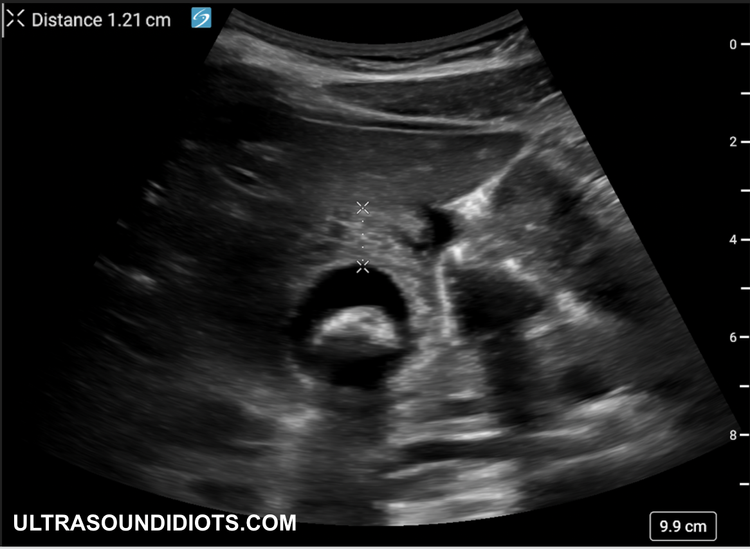

cholecystitis